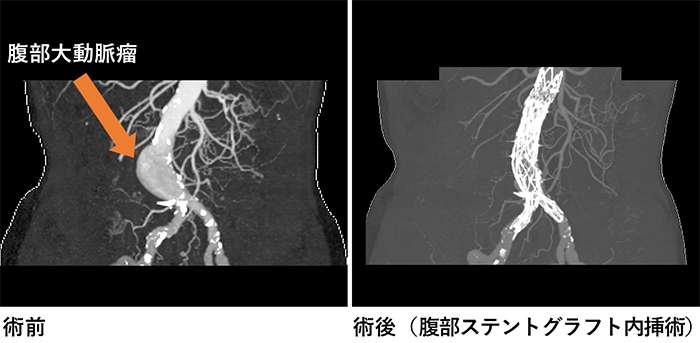

腹部大動脈瘤治療

・当院ではより低侵襲かつ耐久性の高い腹部ステントグラフト内挿術を目指しています。

・原則4泊5日の手術入院で早期社会復帰を達成させます。

・メスで切らない穿刺法のみによるアプローチで整容面も患者さんの満足頂ける治療を提供します。

・放射線科と協力し腹部瘤から分岐する細かい血管をできる限り塞栓する事で遠隔期成績の更なる向上を目指します。

・多種多様なステントグラフトを使用する事により様々なカタチの瘤へなるべく低侵襲な治療を提供します。

・もちろん開腹による従来の腹部大動脈瘤治療にも精通しているため、ありとあらゆる腹部大動脈瘤に対応できると考えております。